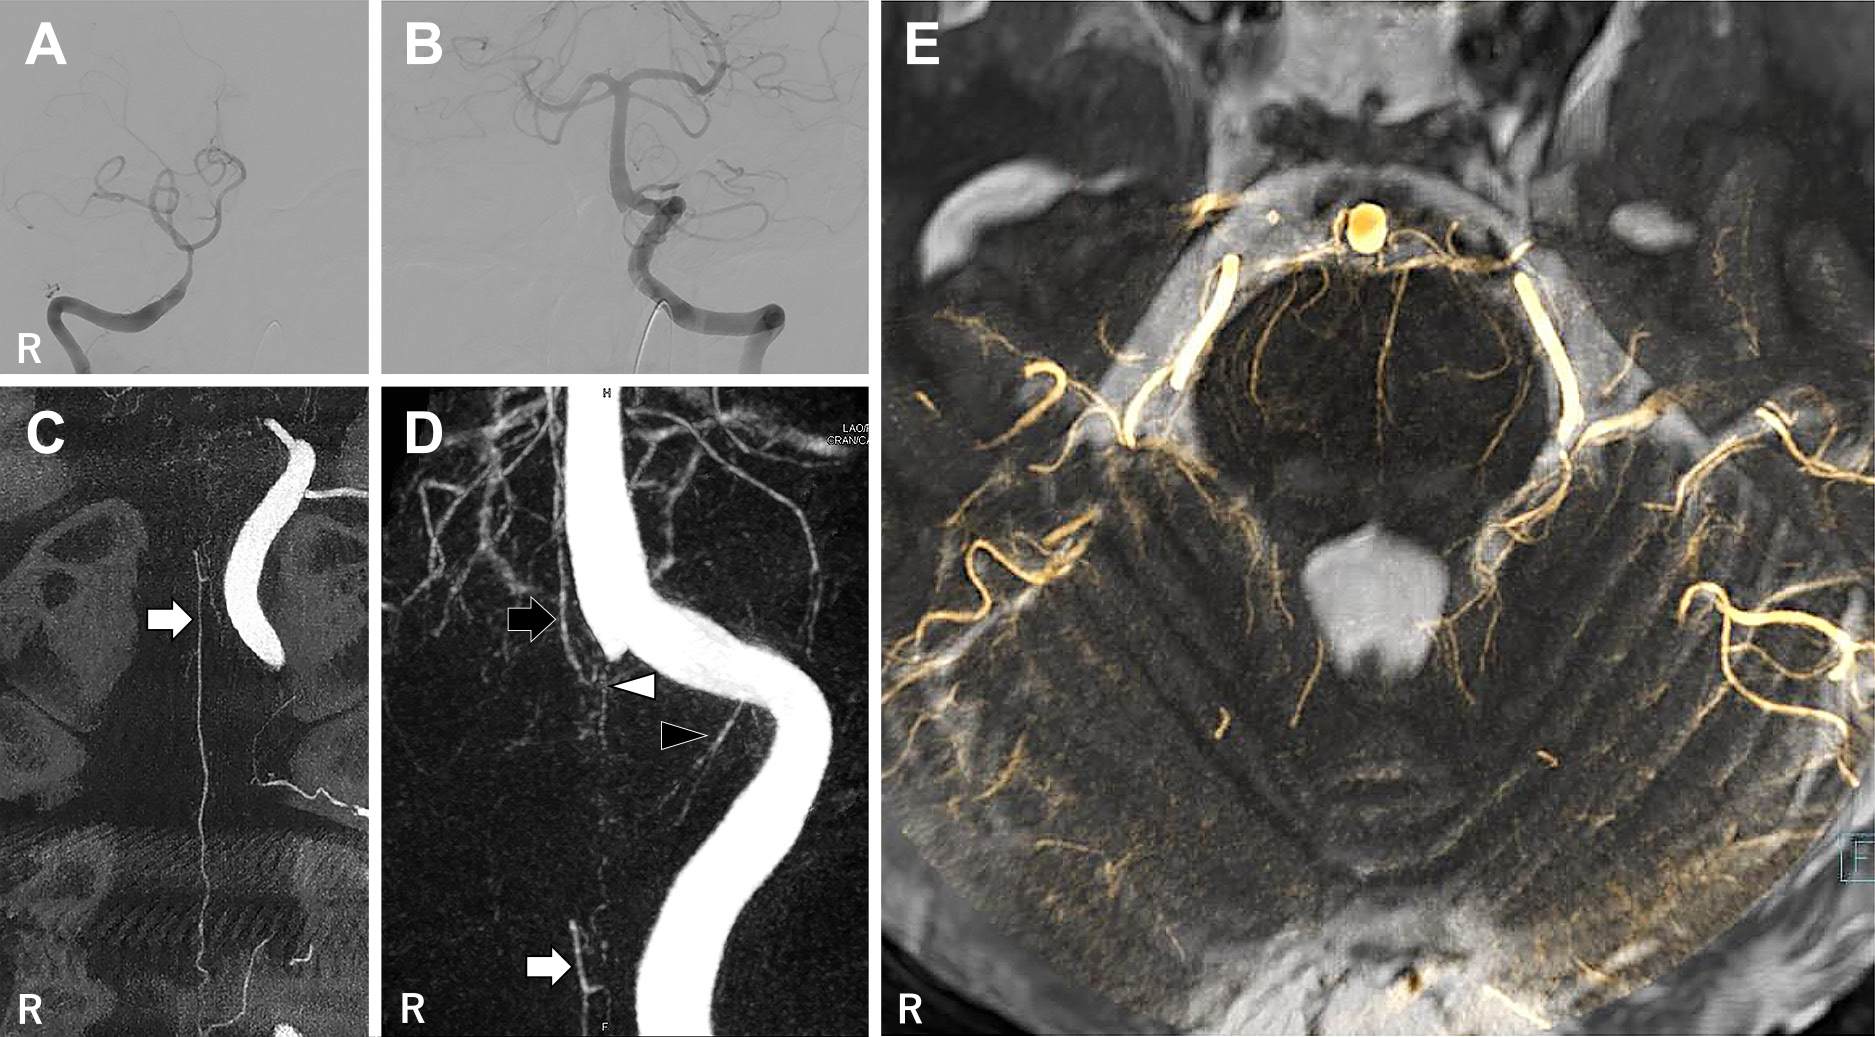

Fig. 3

Digital subtraction angiography (DSA), CT-like image, 3D-reconstruction of CT-like

image and DSA-MR fusion imaging.

A: Right vertebral artery (VA) angiography showed tapered occlusion of the right VA

at the origin of posterior inferior cerebellar artery. B: The left VA angiography

showed no steno-occlusive lesion of the left VA and the basilar artery (BA). C: CT-like

image revealed the anterior spinal artery (ASA) running the dorsal side of the spine

(white arrow). However, the rami of ASA joining to the VA was not observed. In addition,

the ASA was contrasted retrogradely and occluded at the level of the middle medulla

oblongata. D: 3D-reconstruction of CT-like image revealed the right VA perforating

branch (white arrowhead) which arised from distal end of the right VA occlusion, the

BA perforating branch (black arrow) descending nearby VAs union, the left VA perforating

branch (black arrowhead) and the ASA (white arrow). E: The axial view of DSA-MR fusion

imaging at the level of rostral pons. DSA-MR fusion imaging revealed several BA perforating

branches running through pons. White arrow indicates the ASA. White arrowhead indicates

the right VA perforating branch. Black arrow indicates the BA perforating branch.

Black arrowhead indicates the left VA perforating branch.

穿通枝と梗塞の関係を明らかにするために,DSAとMRIのfusion画像を作成した.まず,3D-RAとMRA元画像を頸動脈管と副鼻腔や錐体骨周囲,血管像のズレが5 mm以下となるように手動で位置合わせを行った.次に,ワークステーションの自動位置合わせ機能で角度補正を行った後に,血管像のズレが1 mm以下となるように手動で補正を行い,位置情報の保存を行った.3D-RAとMRIの位置情報は引き継がれるため,3D-RAから骨情報を除去した3D-DSAをT2強調画像と合成した.水平断・冠状断・矢状断の3方向で頭蓋内血管の造影効果とflow voidのズレが1 mm以下であることを確認し,3 mm厚のSlab MIPで処理した画像(DSA-MR

fusion画像)を作成した(Fig. 3E).その結果,両側延髄内側梗塞の正中に右VA閉塞遠位端から分岐した穿通枝が流入していた.しかし,同穿通枝は分岐部の造影効果が弱く,母血管解離による起始部狭窄が考えられた(Fig.

4A, B).BA穿通枝が下降して梗塞近傍に分布していたが,ASAは梗塞中枢側で閉塞していた(Fig. 4C).本症例では右VA解離により,両側支配の右VA穿通枝狭窄とASA閉塞をきたし,橋延髄移行部に広範な梗塞をきたしたと考えられた.